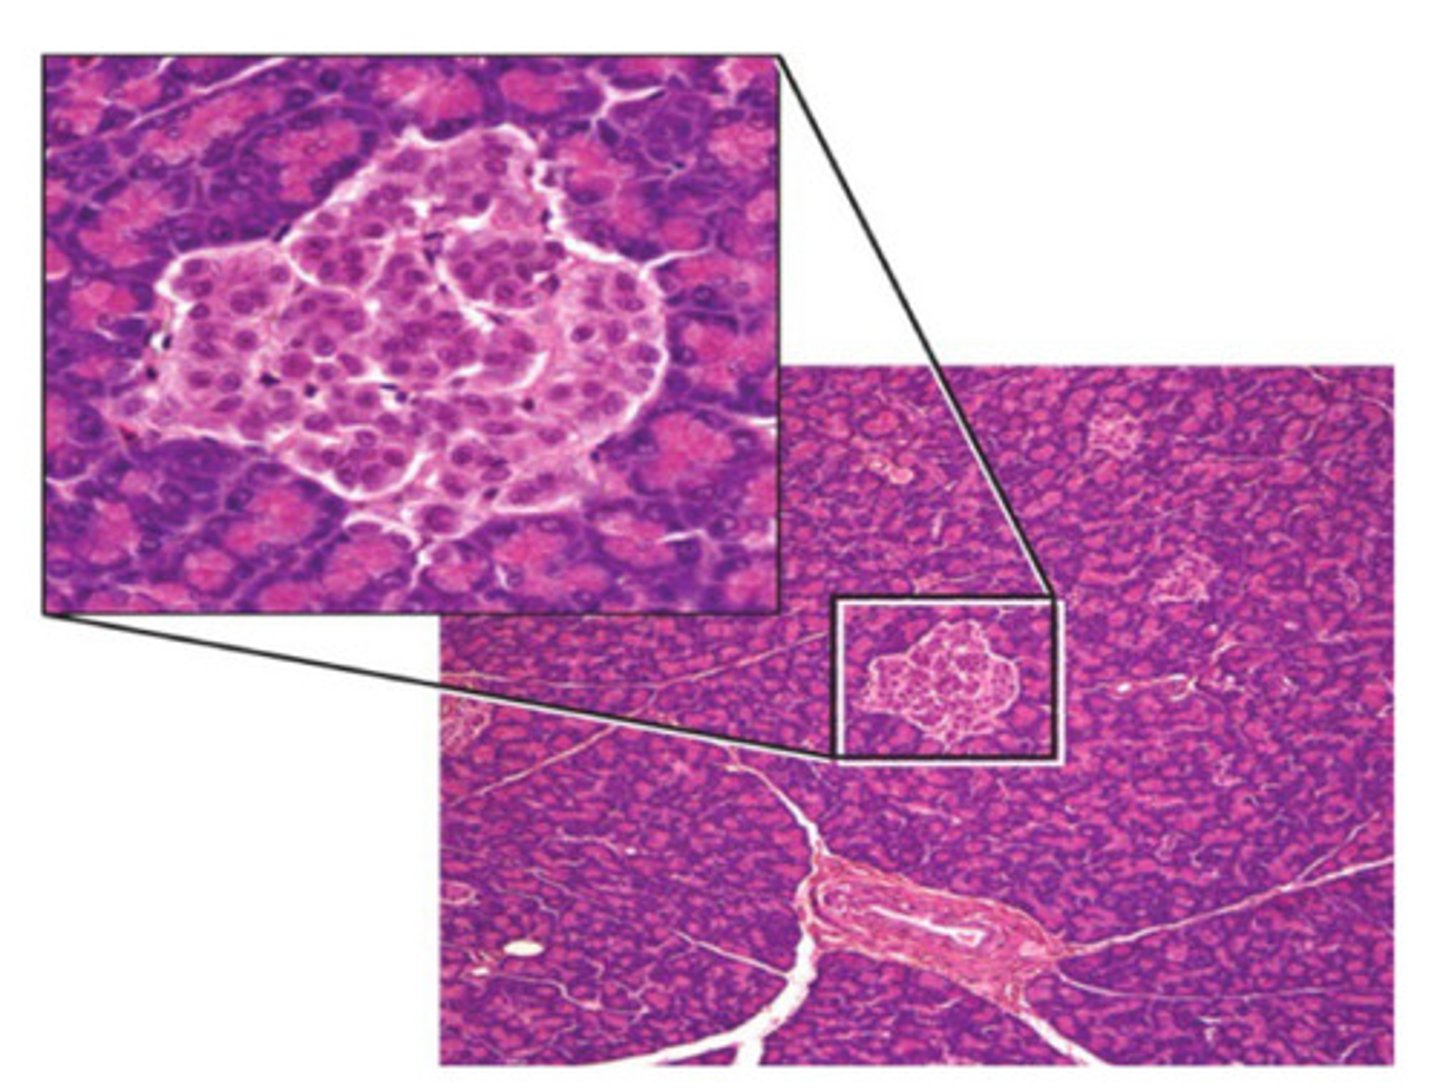

Acini (Pancreas)

darker purple cells that secrete pancreatic juices, found in pancreas

Islets (pancreas)

light purple cells that secrete hormones, found in pancreas